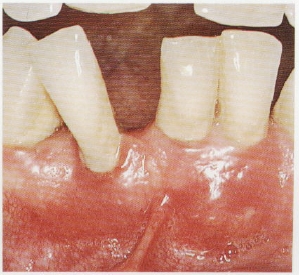

牙龈出血

刷牙出血是牙龈炎症最早且最容易发现的症状,也是牙周组织最先发出的危险警告。如果使用一些含止血成分的药用牙膏,这种牙龈炎症的“报警”就会被掩盖,导致牙周炎症继续进展,进而造成牙槽骨的炎症。